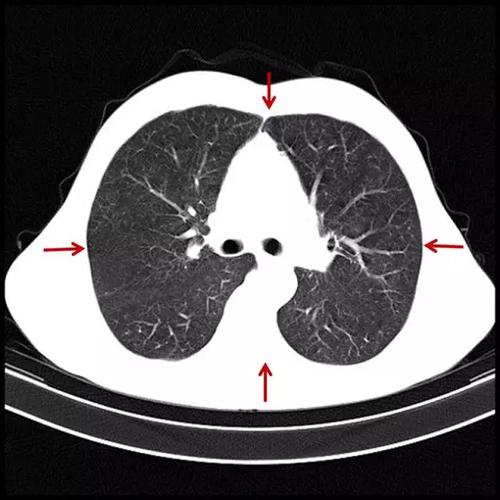

肺气肿CT图片

肺气肿CT图片,肺气肿x线图片

肺气肿的ct表现

肺气肿x线图片

肺气肿的ct图片

肺气肿的ct表现图片